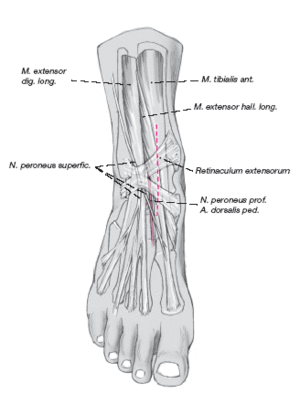

* RMN para determinar la extensión y localización de la lesión (fig. 1).

Figura 1. RMN de tobillo en la que se observa una lesión osteocondral de la porción posterior del astrágalo.